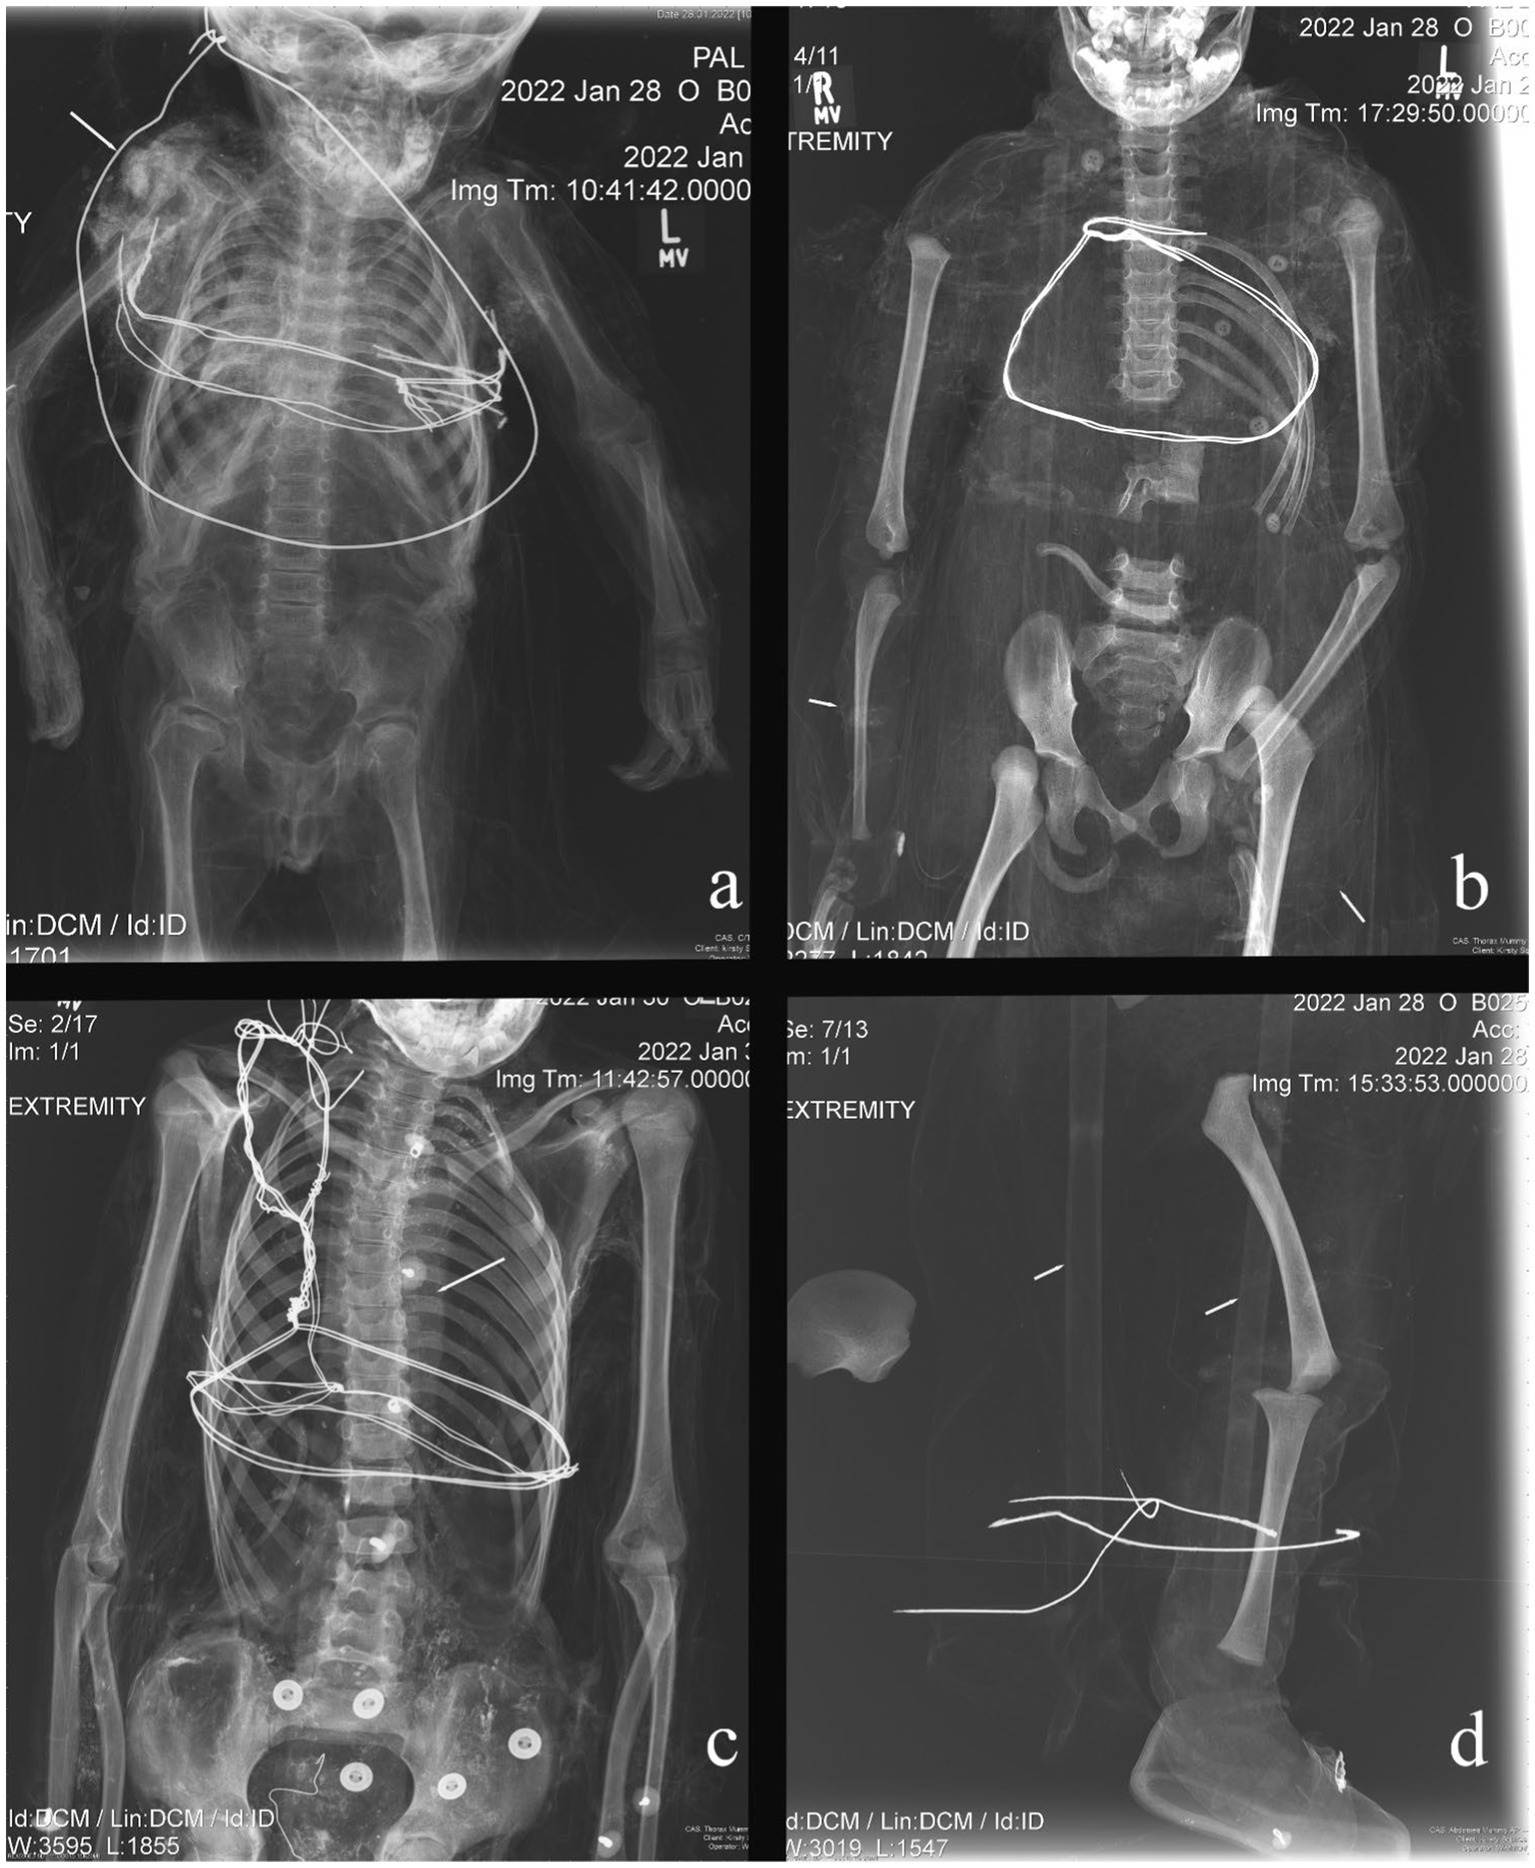

Overall, the individuals examined in this study exhibited little radiographic skeletal pathology and trauma. In total, six non-adults (14.0%) exhibited Harris Lines. Harris Lines were observed in individuals ranging from one and a half years of age to eight years and are most frequently seen in three- to four-year-olds (Figure 1A). Three non-adults showed evidence of more unique pathological conditions. Non-adult B025 presented periosteal reaction on the left proximal humerus, for which the differential diagnosis includes osteomyelitis, Ewing’s tumor, or eosinophilic granuloma, given the location of the lesion and the individual’s age (Figure 1B). Each of these potential diagnoses would have caused pain and therefore, could have led to reduced function and movement. Minor scoliosis was observed in individual B029 (Figure 1C). This was identified by the ‘S’ shaped curve to the spine and was almost certainly asymptomatic. Given the minor nature of the scoliotic curve, it is unlikely that the individual would have been in pain or exhibited an apparent physical deformity. It is thus plausible that the individual could have easily participated in daily activities. Non-adult B035 demonstrated Harris Lines on the proximal and distal tibiae alongside bilateral marked pes cavus deformities, suggestive of a neuromuscular abnormality, including but not limited to polio, Charcot–Marie-Tooth, or cerebral palsy (Figure 1D). The individual would likely have experienced pain with ambulation, not only because of the underlying neuromuscular condition, but also because of the altered mechanics associated with the pes cavus deformity. Individuals with these types of disorders often display an abnormal gait.

Figure 1

Examples of pathological conditions found in the investigated non-adult mummies. (A) B014: Harris Lines; (B) B025: periosteal reaction; (C) B029: scoliosis; (D) B035: pes cavus.